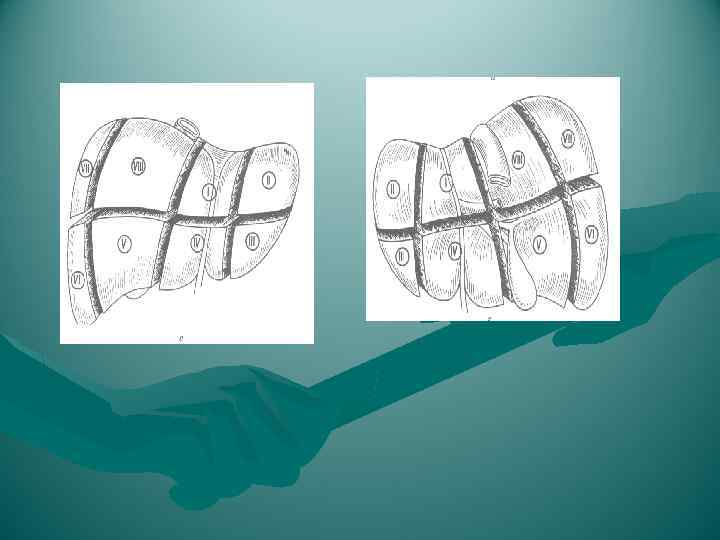

СЕГМЕНТАРНОЕ СТРОЕНИЕ ПЕЧЕНИ Сегмент - участок печени, имеющий до некоторой степени обособленное кровоснабжение, желчный отток и лимфоотток Деление на сегменты с учетом ветвления элементов портальной системы (v. portae, a. hepatica propria, ductus hepaticus) - анатомически более обосновано и чаще используется в хирургической практике. Схема сегментарного строения печени по Couinaud (1957) 2 доли 5 секторов 8 сегментов

СЕГМЕНТАРНОЕ СТРОЕНИЕ ПЕЧЕНИ Сегмент - участок печени, имеющий до некоторой степени обособленное кровоснабжение, желчный отток и лимфоотток Деление на сегменты с учетом ветвления элементов портальной системы (v. portae, a. hepatica propria, ductus hepaticus) - анатомически более обосновано и чаще используется в хирургической практике. Схема сегментарного строения печени по Couinaud (1957) 2 доли 5 секторов 8 сегментов